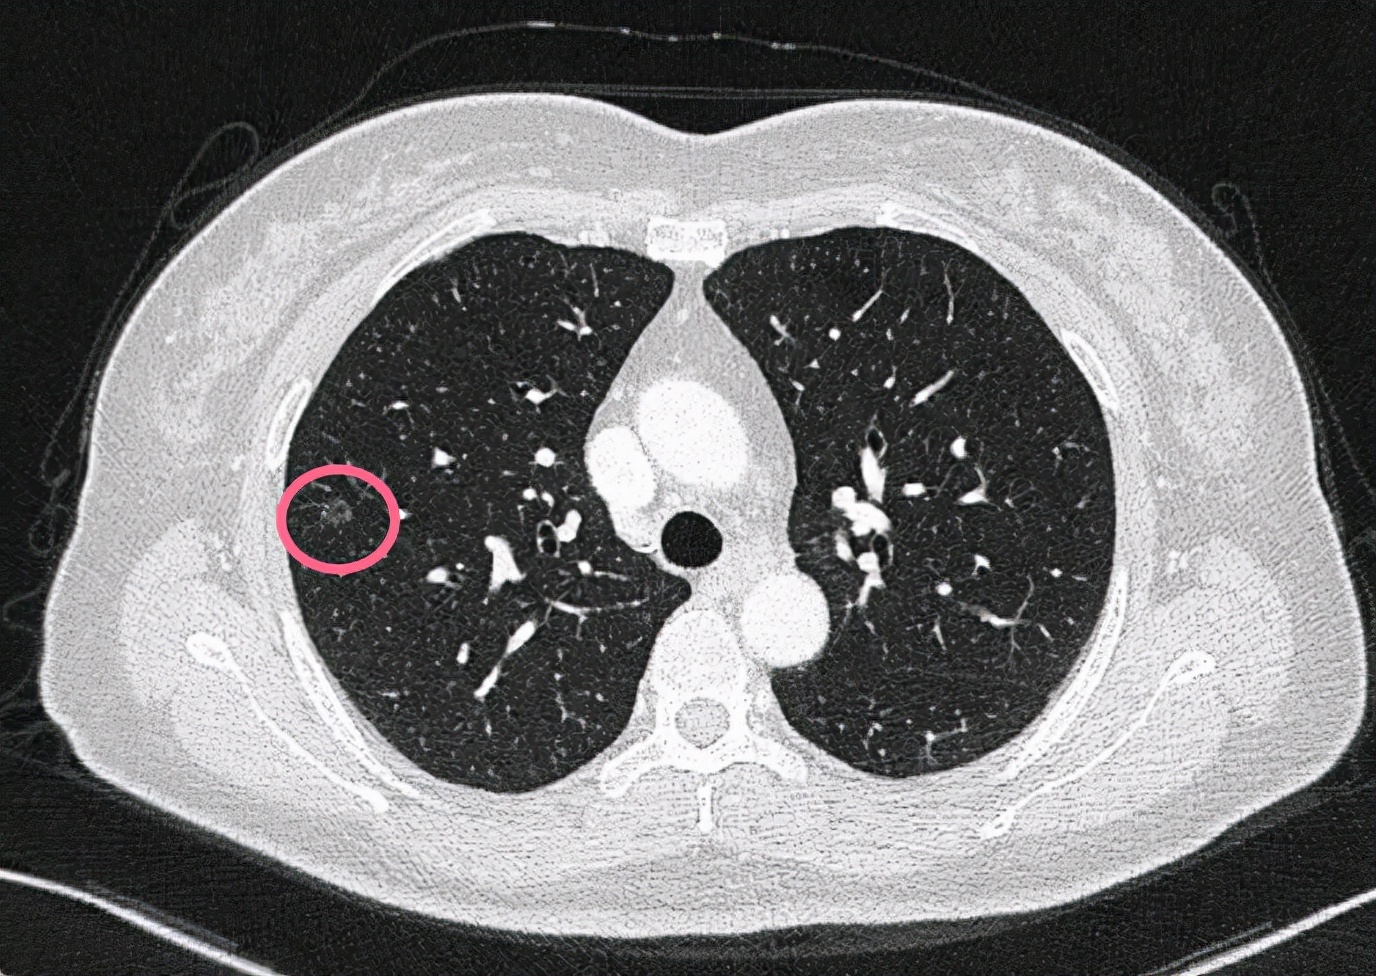

今天一位网络问诊病人,才45岁,没有症状。我们先来看他的CT图像:

右上叶磨玻璃结节,瘤肺边界清,中间伴有小空泡,考虑原位腺癌可能性大,不能完全除外微浸润或不典型增生